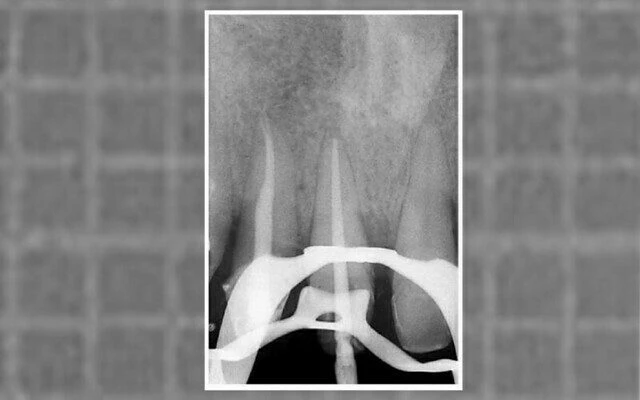

trâm đưa vào xoang tủy

Hình 11.26. A. Một trâm nhỏ đưa vào sau giai đoạn xuyên qua bị cản trở ở phần thân răng, không bị cản hoàn toàn, dụng cụ vẫn đưa vào được trong ống tủy. B. Sơ đồ thể hiện trở ngại mà dụng cụ gặp phải: phần tam giác gần thân răng hơn là  “tam giác # 1”, phần tam giác gần chóp răng hơn là  “tam giác # 2”.